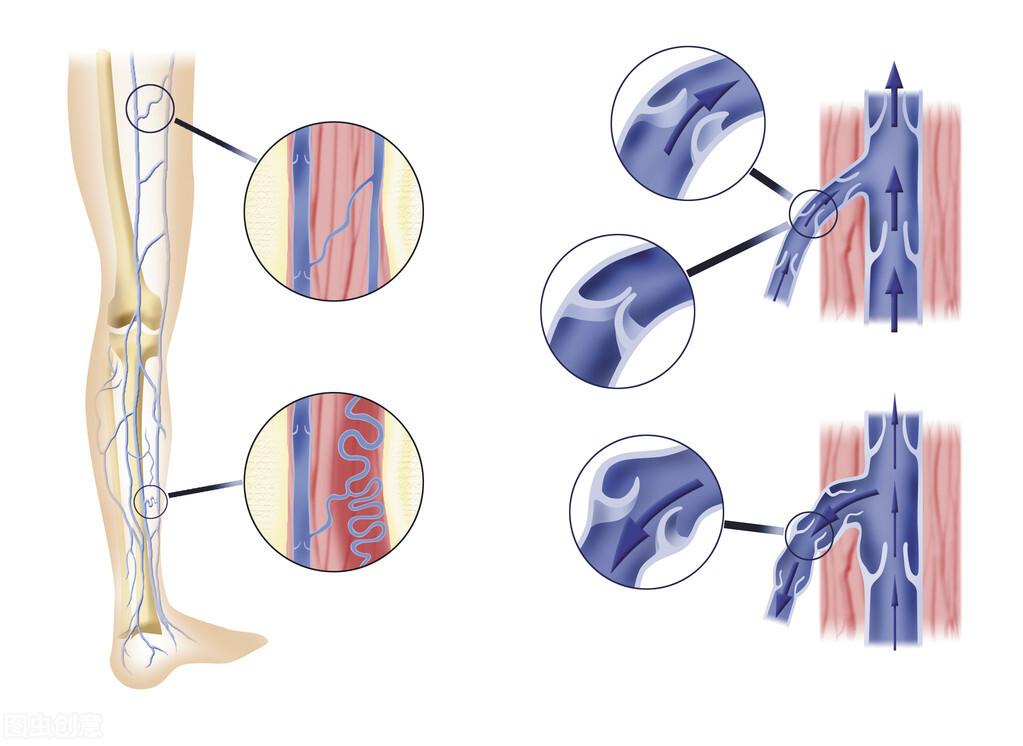

四、小腿肿胀,疼痛:静脉血栓。

特别是有长期静脉曲张的患者发生了下肢肿胀疼痛,一定要考虑是不是血栓形成了。

这种血栓往往都是静脉血栓,而且经常发生在小腿。

出现静脉血栓一定要去血管外科看一下。

医生经常会建议患者做下肢的彩超,看看两条腿的静脉有没有问题。

如果真的有血栓,会根据血栓的具体情况采取治疗措施,要么吃抗凝溶栓的药物,要么做简单的微创手术治疗。